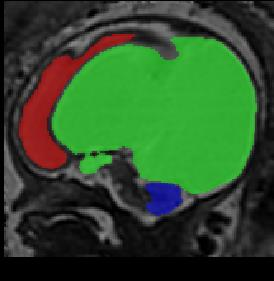

Limiting failures of machine learning systems is of paramount importance for safety-critical applications. In order to improve the robustness of machine learning systems, Distributionally Robust Optimization (DRO) has been proposed as a generalization of Empirical Risk Minimization (ERM). However, its use in deep learning has been severely restricted due to the relative inefficiency of the optimizers available for DRO in comparison to the wide-spread variants of Stochastic Gradient Descent (SGD) optimizers for ERM. We propose SGD with hardness weighted sampling, a principled and efficient optimization method for DRO in machine learning that is particularly suited in the context of deep learning. Similar to a hard example mining strategy in practice, the proposed algorithm is straightforward to implement and computationally as efficient as SGD-based optimizers used for deep learning, requiring minimal overhead computation. In contrast to typical ad hoc hard mining approaches, we prove the convergence of our DRO algorithm for over-parameterized deep learning networks with ReLU activation and a finite number of layers and parameters. Our experiments on fetal brain 3D MRI segmentation and brain tumor segmentation in MRI demonstrate the feasibility and the usefulness of our approach. Using our hardness weighted sampling for training a state-of-the-art deep learning pipeline leads to improved robustness to anatomical variabilities in automatic fetal brain 3D MRI segmentation using deep learning and to improved robustness to the image protocol variations in brain tumor segmentation. Our code is available at https://github.com/LucasFidon/HardnessWeightedSampler.